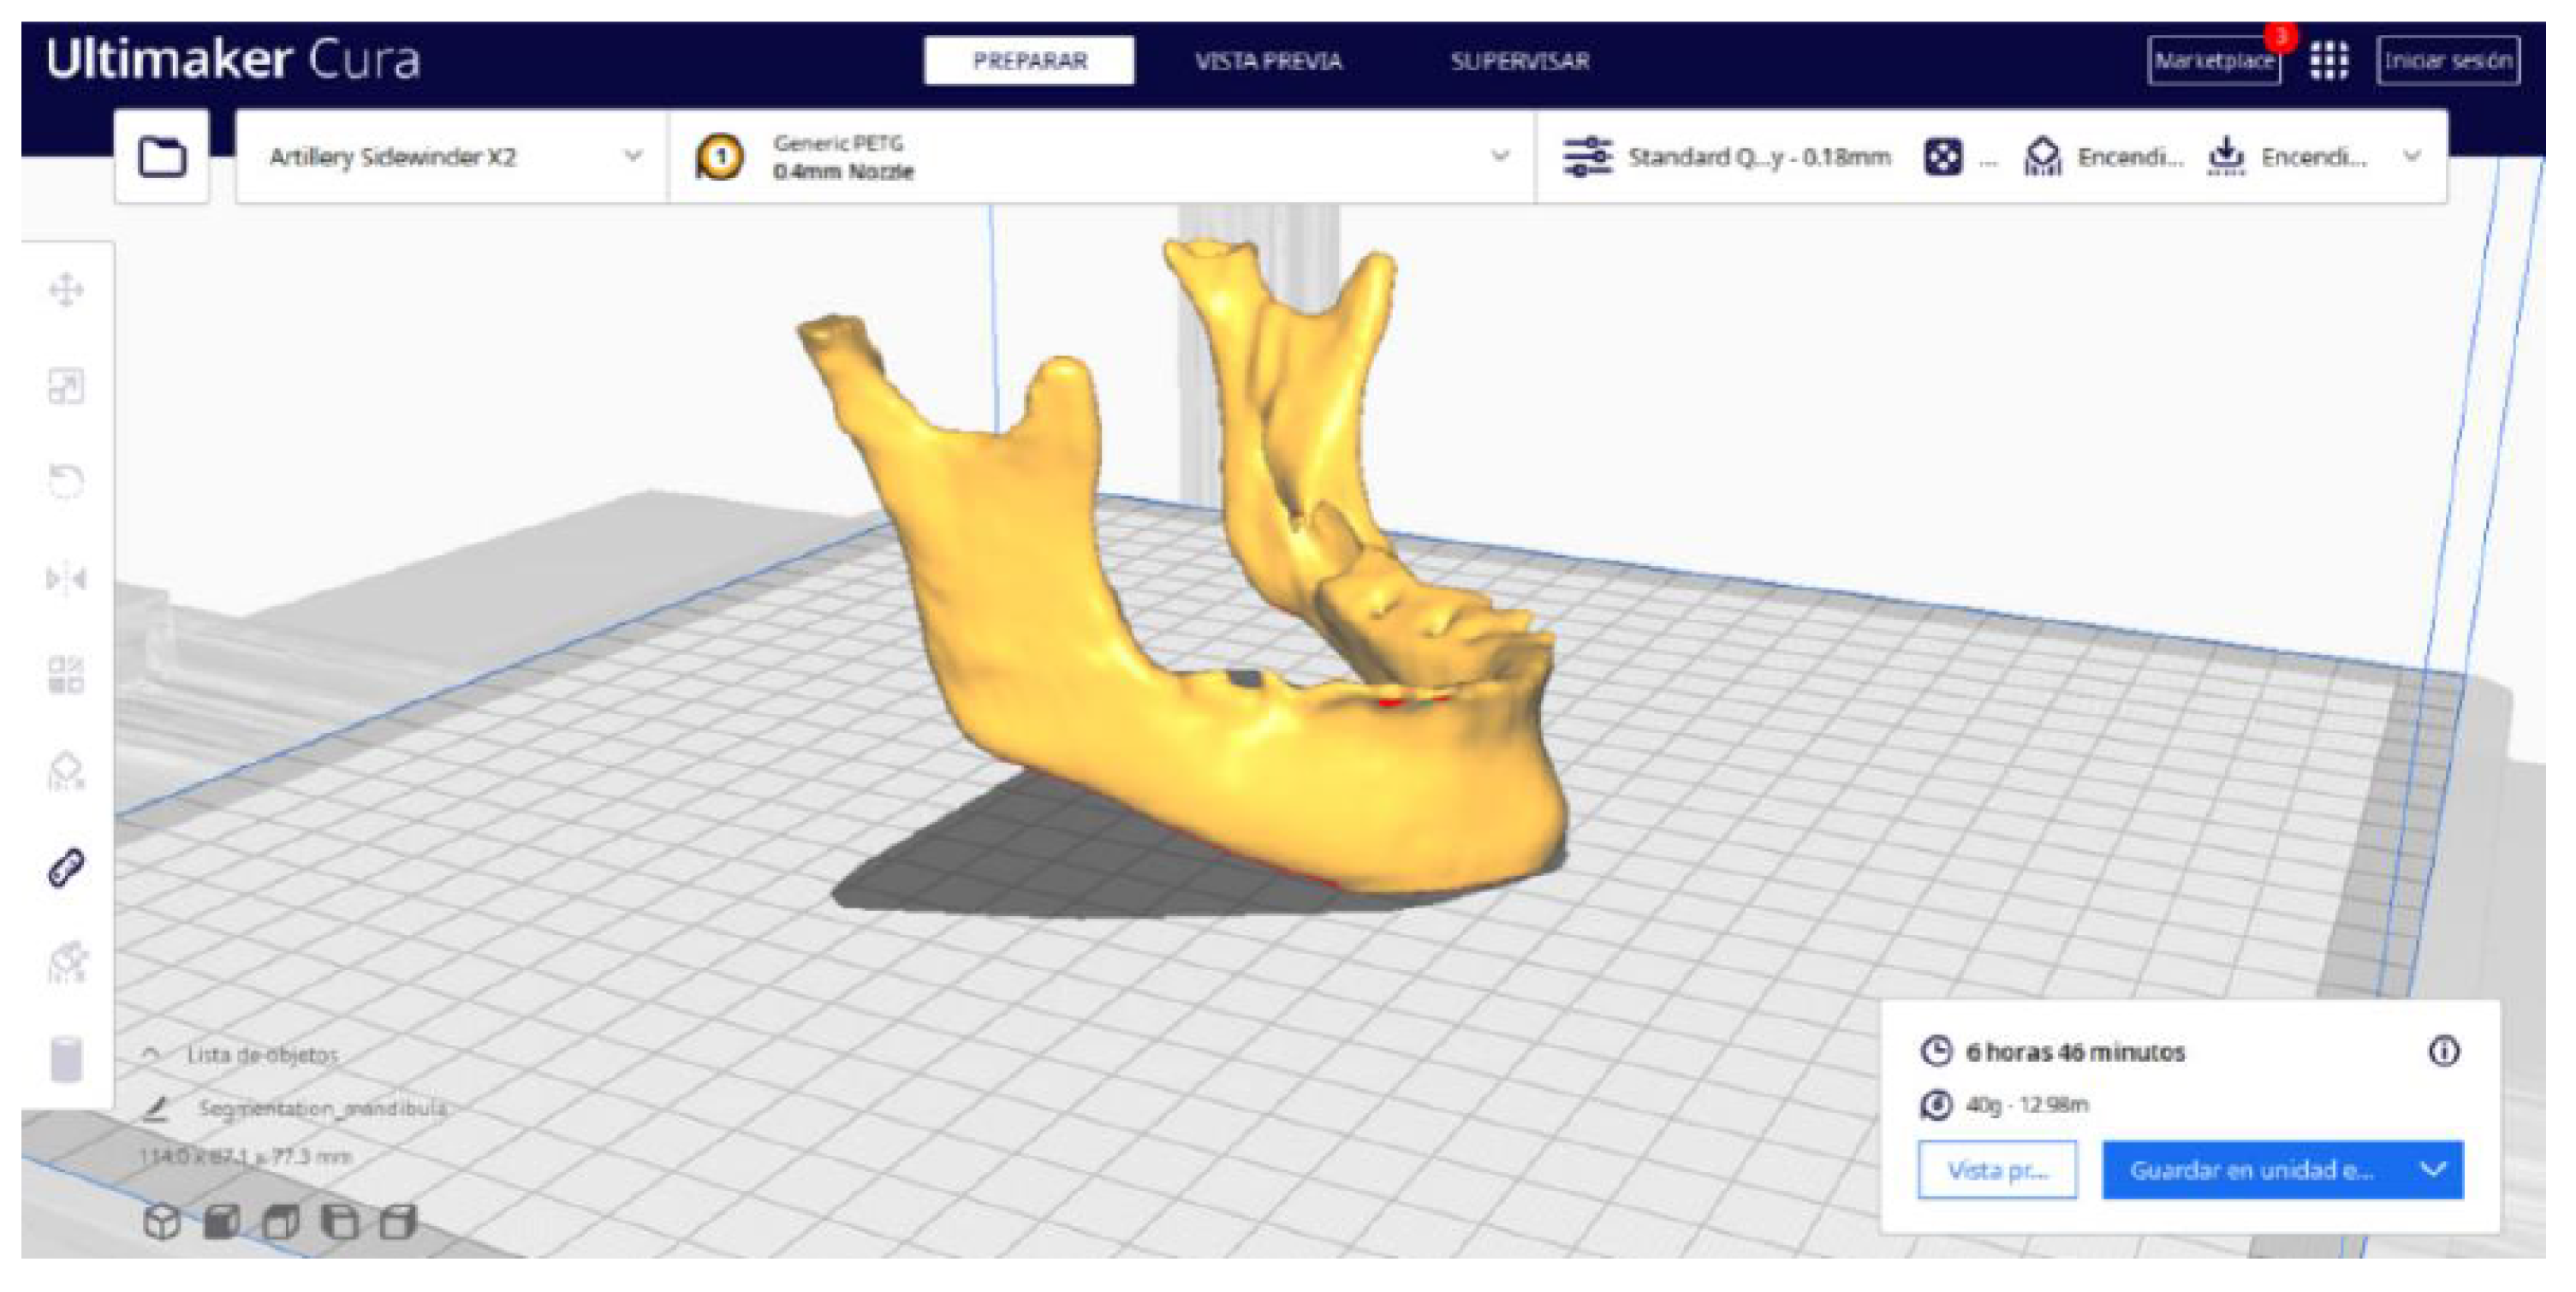

3.2.2. STL-to-GCODE Files

2.2. STL-to-GCODE File Conversion

- Launch the Ultimaker Cura program on your computer.

- Open the STL file you want to print from the “Open File” option in the menu.

- Access the printer settings within Ultimaker Cura.

- Be sure to select the appropriate printer model and material settings for your 3D printer.

- If necessary, make adjustments to the position, scale, or rotation of the model on the build platform within Ultimaker Cura. This allows you to optimise the layout of the model on the printing platform.

- Adjust the layer height and line width to refine the print quality, considering the balance between print resolution and time efficiency.

- Choose the appropriate support structure type and pattern to ensure the successful printing of complex geometries, adjusting the adhesion to the build plate as necessary.

- In order to continue the STL file to GCODE conversion process, select the “Segmentation” option in Ultimaker Cura.

- The segmentation tool provides valuable information such as the estimated model weight and estimated printing time, among other crucial data.

- Once the segmentation is complete, go to the “Preview” option. Here, a sidebar will appear on the right side of the screen, giving you the ability to preview the materialisation process layer by layer, from the base to the top of the model.